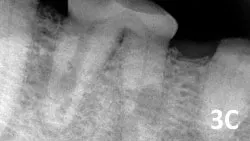

Internal inflammatory resorption (See Figures 3B and 3C) ischaracterized by an oval-shaped enlargement typically found in the coronal third of the tooth and results from active inflammation secondary to trauma. Treatment options are either extraction or root canal therapy, if the lesion has not progressed to perforation of the root.

A dental radiograph shows a close-up view of a canine tooth with evidence of periapical radiolucency, indicating possible dental disease. The surrounding bone structure appears intact, highlighting the area of concern near the root apex.

Figure 3C

Internal resorption of the mesial and distal roots.